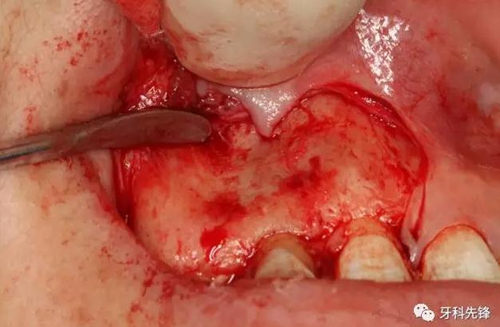

圖5.唇側(cè)梯形切口。

圖6.翻瓣、暴露術區(qū)、唇側(cè)骨板未破壞。

圖7.唇側(cè)骨板完整無缺。